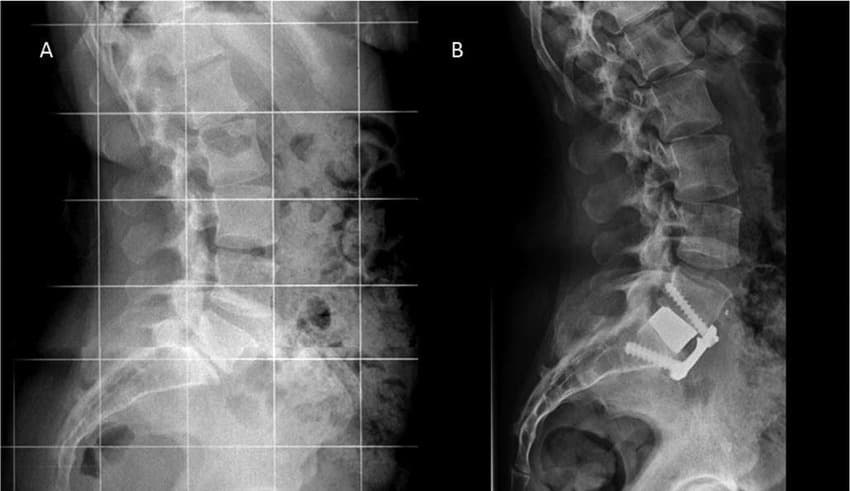

During an ALIF, the surgeon makes an incision in the abdomen. The abdominal muscles and internal organs are carefully moved to the side to access the front of the spine. Once the spine is exposed, the surgeon removes the damaged or degenerated intervertebral disc. A specialized metal spacer is filled with bone graft material and then inserted into the empty disc space. This restores the disc height and natural curve of the spine. Over several months, the bone graft fuses with the adjacent vertebrae, creating a single, solid bone segment. Because the anterior approach avoids major back muscles, it often results in less post-operative pain, reduced blood loss, and a shorter recovery time compared to traditional fusion surgeries. Additionally, the natural curve of the spine and disc height can be better restored to their native condition.

Anterior lumbar interbody fusion (ALIF) is a type of spinal fusion surgery that approaches the spine from the front (anterior) of the body. The goal of the procedure is to stabilize the spine and alleviate pain by fusing two or more vertebrae.